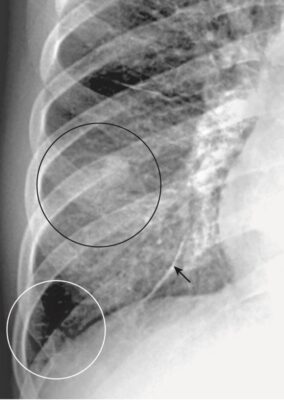

Hít phải (Aspiration)

- Hít phải có xu hướng ảnh hưởng đến bất kỳ phần nào của phổi nằm thấp nhất vào thời điểm bệnh nhân hít phải, và các biểu hiện của nó phụ thuộc vào (các) chất được hít vào. Đối với hầu hết các bệnh nhân nằm giường, hít phải thường ảnh hưởng đến các thùy dưới hoặc phần sau của thùy trên.

- Do đặc điểm về đường đi và kích thước của phế quản chính bên phải, hít phải thường xảy ra ở thùy dưới bên phải hơn là thùy dưới bên trái (Hình 7 ).

- Hình ảnh chụp X quang của hít phải và bệnh khỏi nhanh như thế nào tùy thuộc vào loại chất hít phải và có bị nhiễm trùng hay không. Hít phải dịch vị sạch hoặc nước thường sạch nhanh trong vòng 24 đến 48 giờ, trong khi hít phải bội nhiễm có thể mất vài tuần mới khỏi.